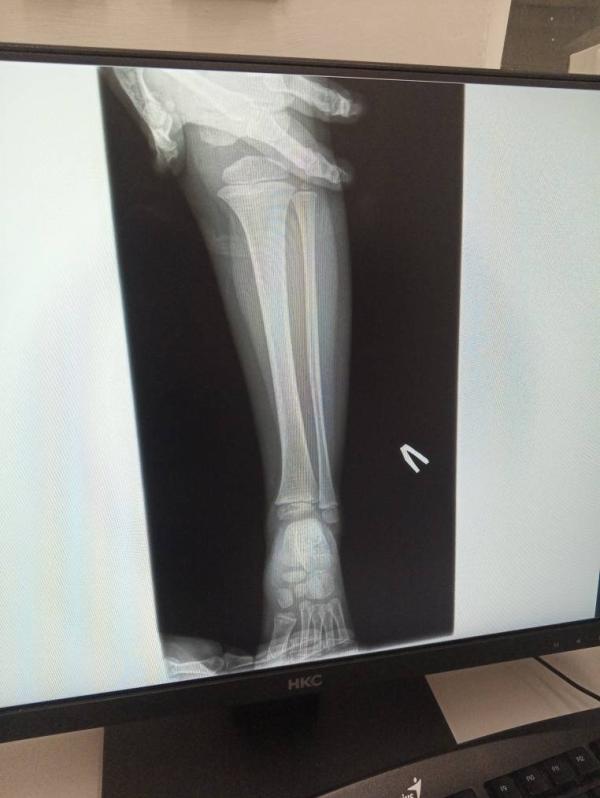

Снимок вчера сделали , перелом яц аьл отправили домой, но и цу те да ц хут, йа куьг ц 1утит, просто йоьлх са кхачин са цо, ху дир дар те((